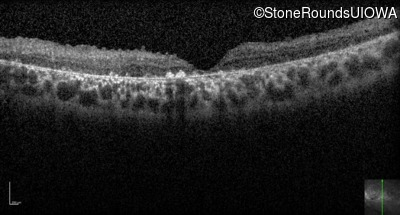

Optical Coherence Tomography - Left - 10/700 sc

Exemplar / OCT Stack